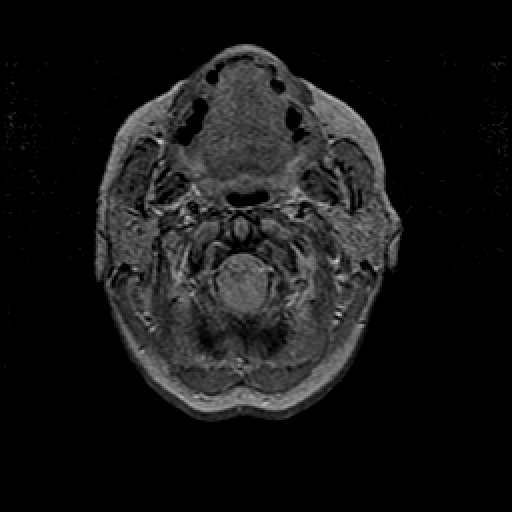

Proton density-weighted structural MR: Slice 3

Slice 3